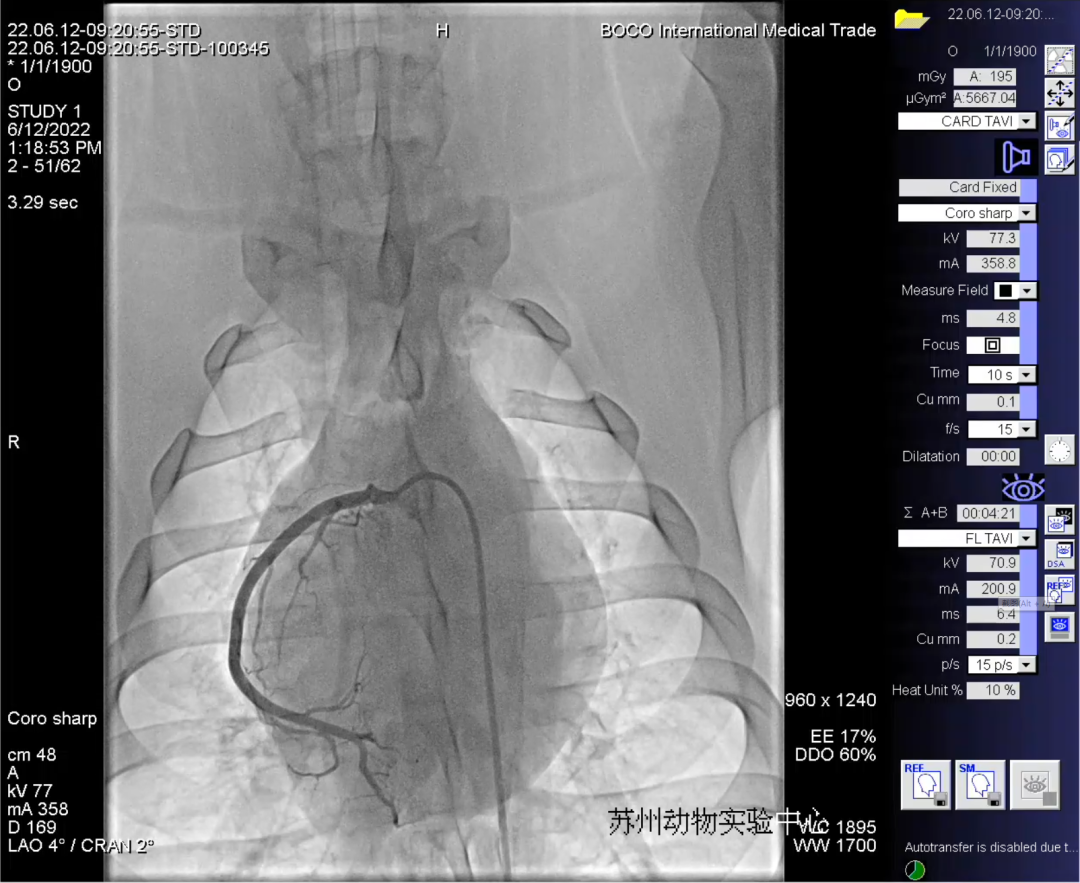

本次动物实验成功完成了两例实验用猪的左、右冠状动脉造影、并于一例实验用猪的左冠血管植入支架。实验中分别采用多种器械组合进行了相同术式操作,均取得成功,充分验证了微亚医疗血管介入机器人远程手术的安全性、稳定性和场景适用性。

“微亚冠通”血管介入手术机器人通过深度优化的指令传输系统,结合超低延时的DSA影像传输系统,有效确保了术者的动作指令和观察影像的同步,达到与本地操作无差异感的体验。